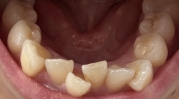

叢生を直したくて、歯列矯正専門歯科で精密検査を受けました。

右上は2番を抜歯、左上は4番を抜歯、下に関しては上の様子を見てそのうち片側の4番か前に出ている1番どちらか1本の抜歯になると言われました。

画像1

画像2

写真拝見しました、写真から伺えることは右上2番の抜歯は避けられないように思います、右下1番も抜歯になる可能性は高いように思います。

上顎側切歯が口蓋側に転移しており、犬歯と中切歯との間にスペースないという症例は時々拝見することがあります。

とはいっても、現状のお写真からすれば、移転歯の可能性は低そうに思えます。